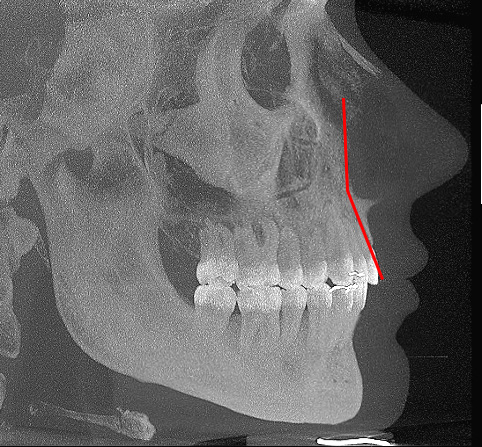

The maxillary region above the white line is technically under projected and set back compared to the teeth/lower maxilla. This results in a low angle between upper maxilla and lower maxilla (red lines above).

Now if the upper maxilla, paranasal and canine fossa were not recessed, the angle between upper maxilla and lower maxilla is made much smaller (red lines below). Facial tissue will run harmoniously between the midface and the lips.

Bbhj

Folds are far less likely to occur in those with well projected mid faces. This is a big reason people who are not "recessed" can have nasolabial folds... they have some degree of recession in the paranasal and midface area compared to the lower maxilla. Dr Ramieri has also spoken about this and how bimax is not a solution for this.